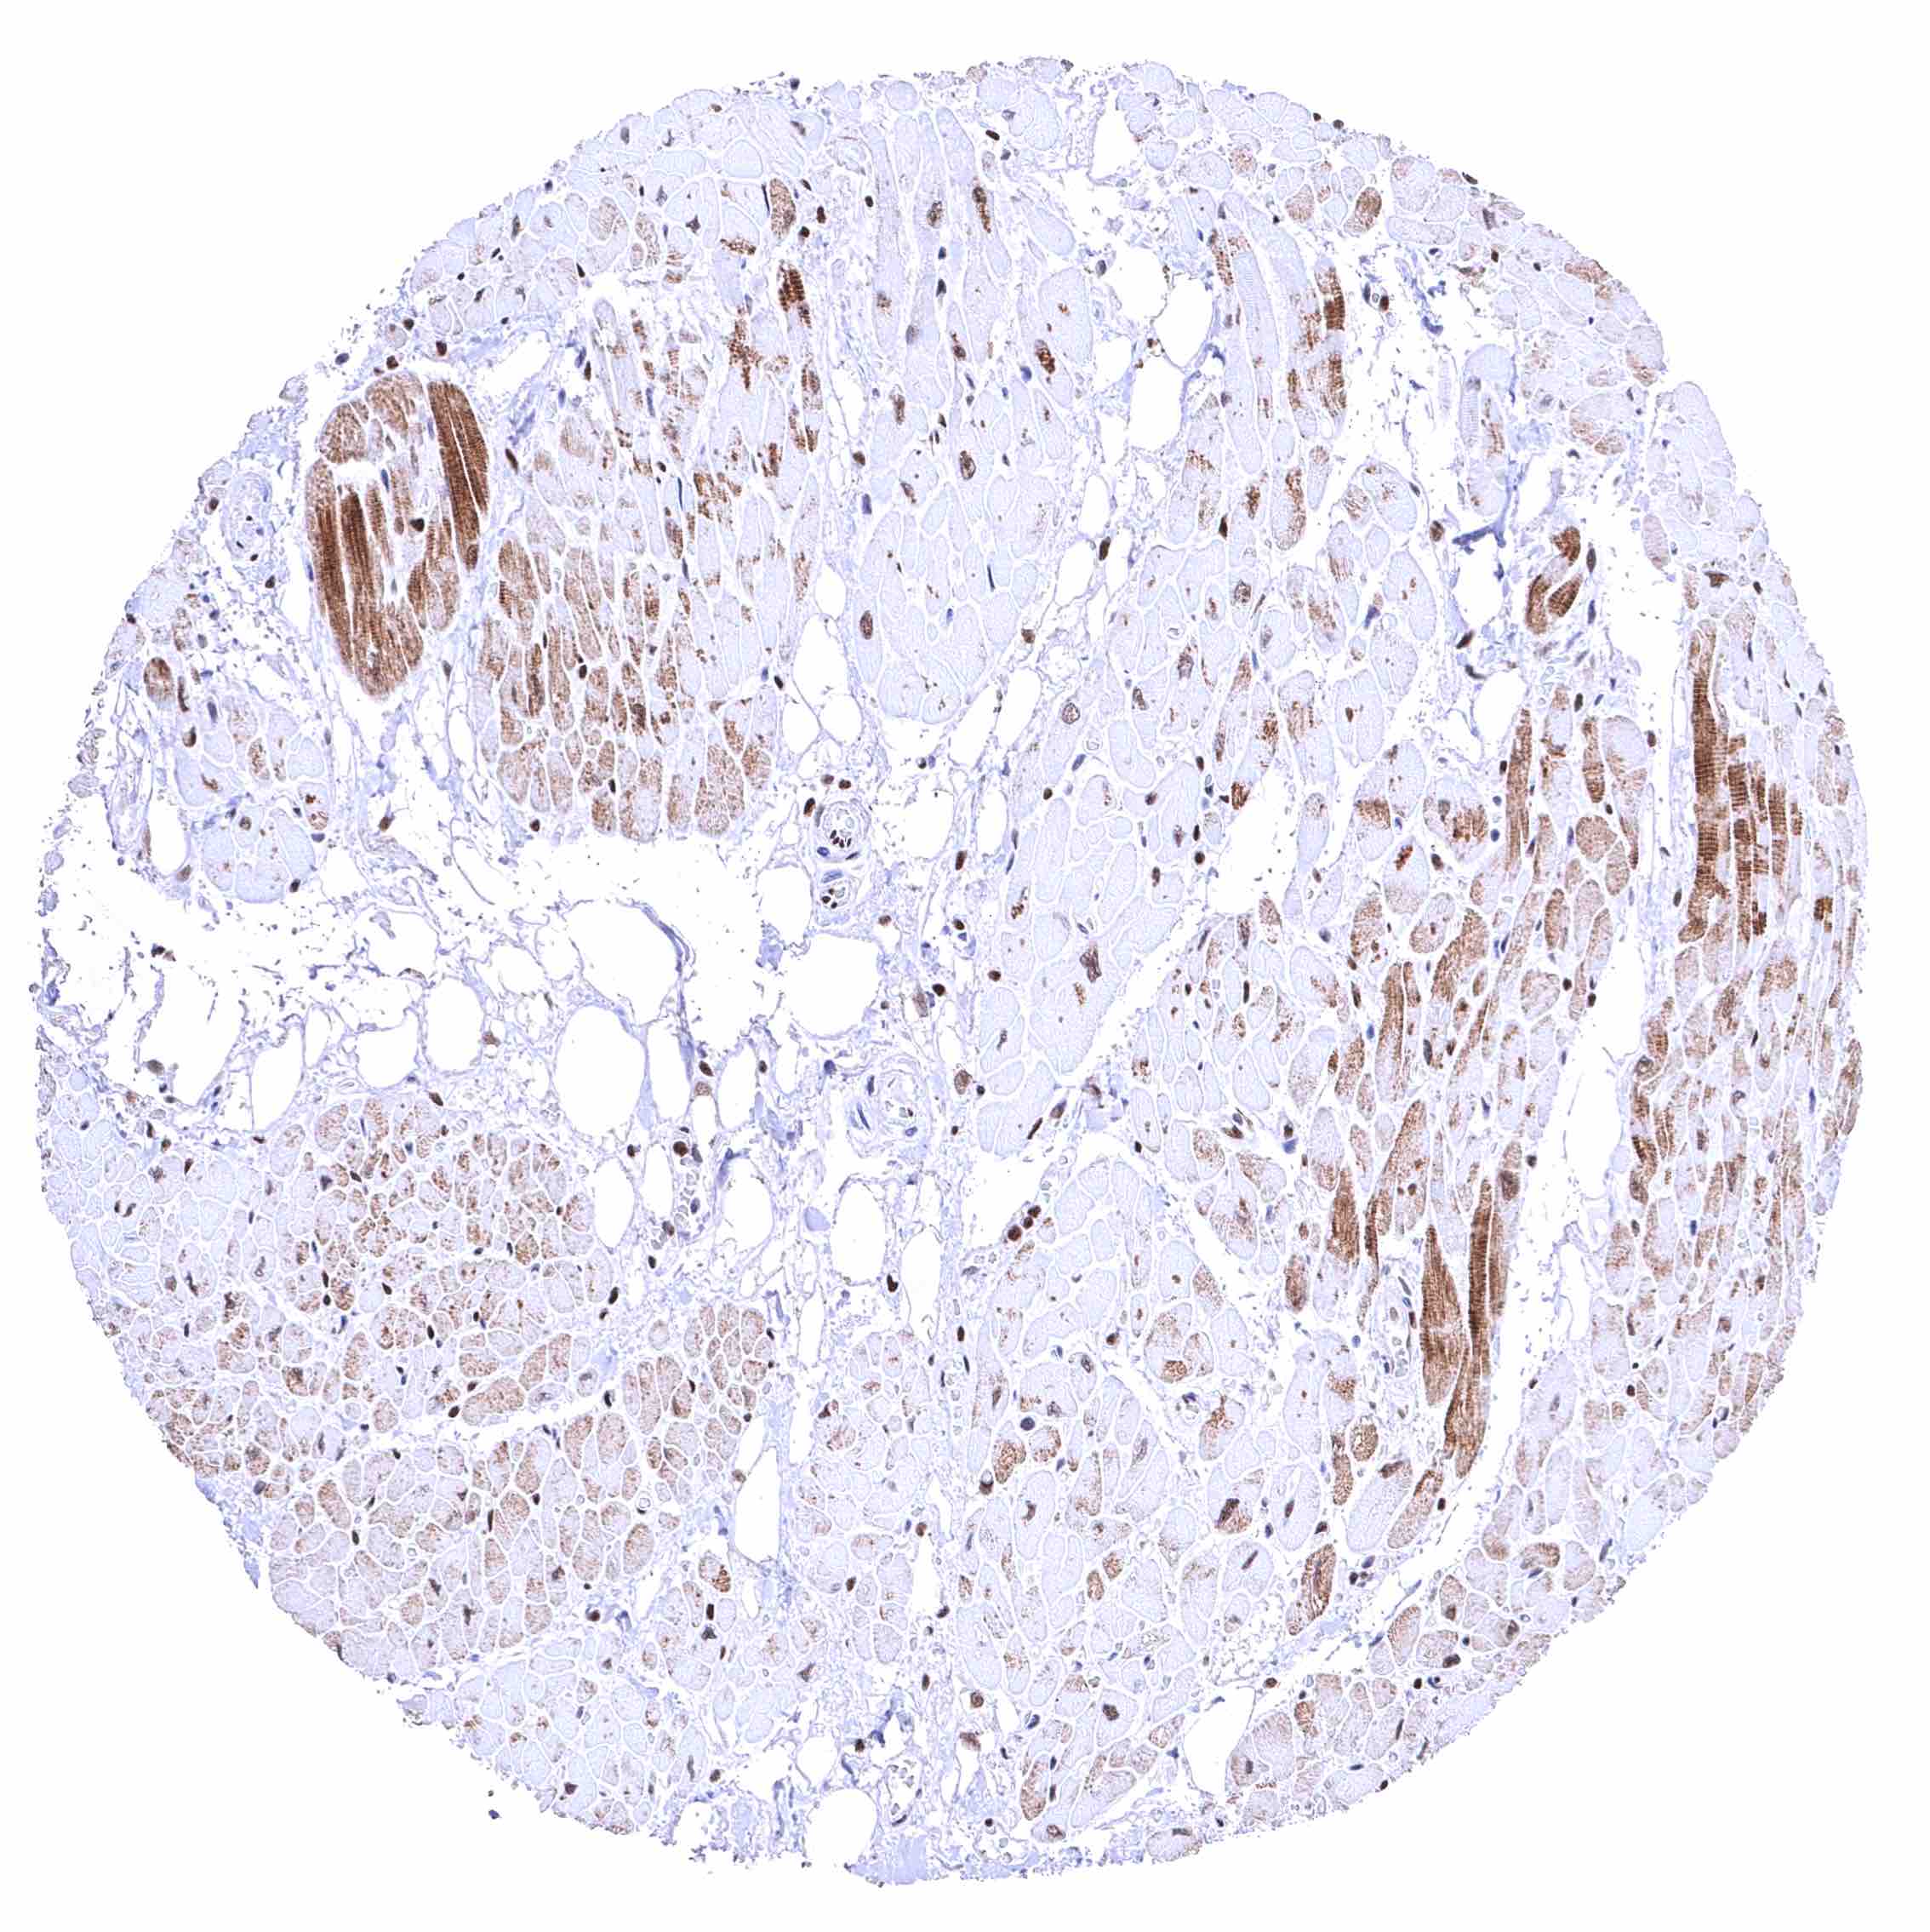

Skeletal muscle – Distinct nuclear BRD4 staining of all cells. The additional cytoplasmic staining of some muscle cells may represent an antibody specific cross-reactivity.

Skeletal muscle – Distinct nuclear BRD4 staining of all cells. A cytoplasmic staining of muscle cells is not seen in this sample.